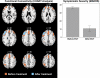

To date, electroconvulsive therapy (ECT) is the most potent treatment in severe depression. Although ECT has been successfully applied in clinical practice for over 70 years, the underlying mechanisms of action remain unclear. We used functional MRI and a unique data-driven analysis approach to examine functional connectivity in the brain before and after ECT treatment. Our results show that ECT has lasting effects on the functional architecture of the brain. A comparison of pre- and posttreatment functional connectivity data in a group of nine patients revealed a significant cluster of voxels in and around the left dorsolateral prefrontal cortical region (Brodmann areas 44, 45, and 46), where the average global functional connectivity was considerably decreased after ECT treatment (P < 0.05, family-wise error-corrected). This decrease in functional connectivity was accompanied by a significant improvement (P < 0.001) in depressive symptoms; the patients' mean scores on the Montgomery Asberg Depression Rating Scale pre- and posttreatment were 36.4 (SD = 4.9) and 10.7 (SD = 9.6), respectively. The findings reported here add weight to the emerging "hyperconnectivity hypothesis" in depression and support the proposal that increased connectivity may constitute both a biomarker for mood disorder and a potential therapeutic target.